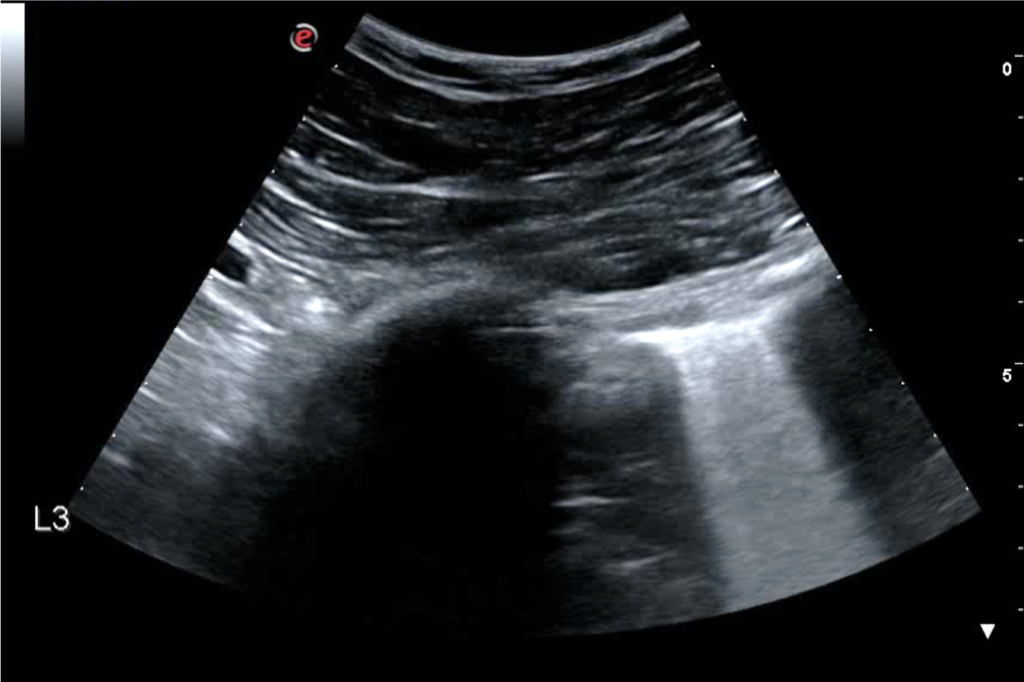

A 30-year-old man presents to the emergency department (ED) due to syncope. For the last 10 days he had had fever, cough and dyspnea. At the ED his peripheral oxygen saturation was 86%, BP 130/80, HR 88bpm, RR 20 /min and his temperature 37.4°C. He was given oxygen via a mask. Chest CT was performed and later lung ultrasound (LUS) was performed in 12 areas longitudinal/oblique views using a convex array probe followed by a linear array probe for details (figure 1).

The patient tested positive for SARS-COV-2. On day 2 after admission the patient’s condition deteriorated, and he was transferred to the ICU. Another chest CT was performed. We show the ultrasound and CT images with corresponding legends (image 1-7 + video 1) and discuss the findings in relation to the diagnostic work-up of COVID-19 pneumonia.

On imaging, initial lesions are usually peripheral because SARS-COV-2 attacks the small distal airways. Several reports have described the findings in chest CT. Most commonly few, small, segmental ground glass opacities are seen peripherally and basal. These may deteriorate to become bilateral and multisegmental and finally consolidation and/or ARDS. Most common LUS signs are: vertical pleurogenic artifacts with varying degree of intensity (from few to confluent). These alternate with clear demarcation to A-lines in the same area, especially in the mid- and upper lung. Pleural thickening, sometimes marked, due to the presence of numerous, small subpleural consolidations. Lobar or translobar consolidations of large size and minimal pleural effusions. The LUS features match with the site and kind on CT.

LUS is an examination, which can be carried out bedside. It may provide early information of presence of diffuse multifocal pneumonia (as in COVID-19) and its deterioration (enlarging consolidations). By doing LUS in cases with COVID-19 pneumonia, transport of patients through the hospital and unnecessary exposure of staff and other patients is avoided. Similar LUS signs as the ones described have been observed in other kinds of viral epidemic pneumonia. If they, individually or in combination, have some specificity for COVID-19 pneumonia it should be established with further appropriate studies.